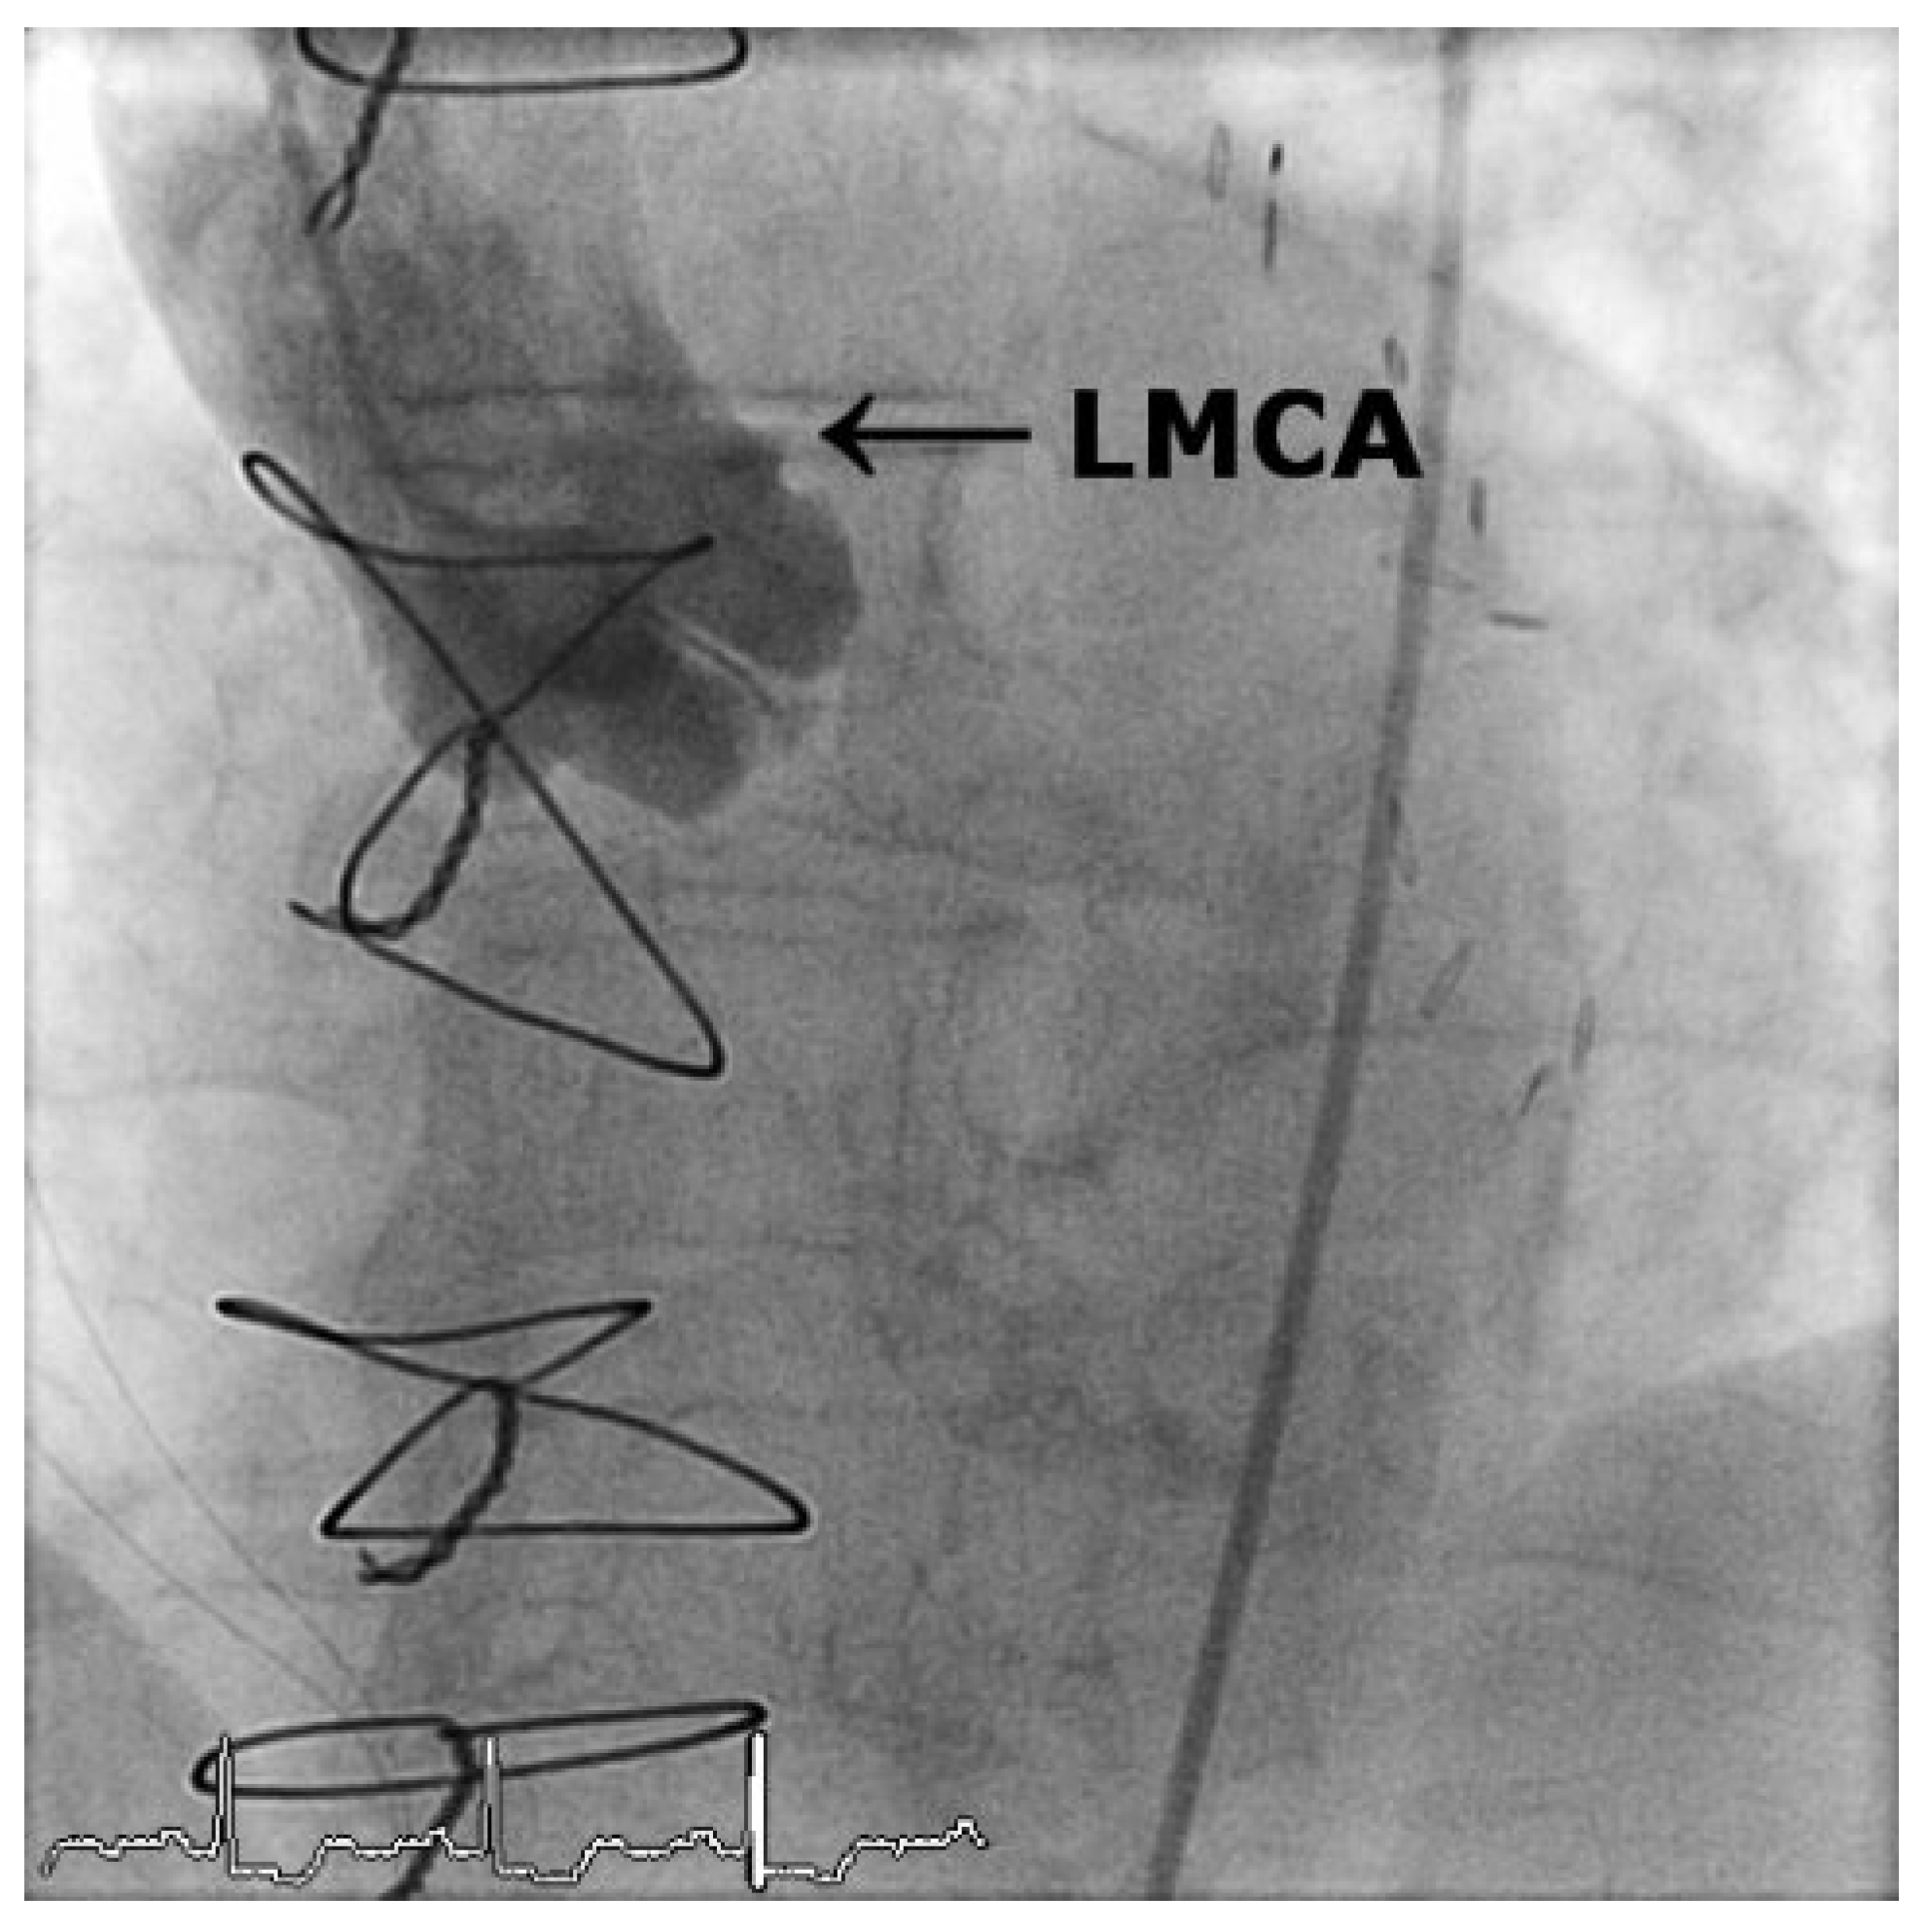

Case2